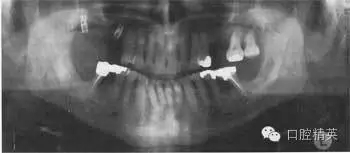

圖38.3 牙齒全口牙位曲面體層X線片顯示的治療結(jié)果

答:全口牙位曲面體層X線片不是很清晰。患者頭位沒擺正,使圖像產(chǎn)生很大扭曲。下頜骨下緣呈彎曲圖像,且下前牙被縮短了。因?yàn)轶w位不正,脊柱陰影也被增強(qiáng)了。因?yàn)橛跋裰丿B,中線處的牙齒沒在中點(diǎn)。頭偏向一邊,一側(cè)影像被放大。這在后牙牙冠上很容易看出來,因?yàn)橛覀?cè)比左側(cè)的牙冠大?;颊叩男g(shù)后片如圖38.3,它顯示了正常片子應(yīng)顯示的樣子。

患者接受了一系列治療,療效如圖38.3。左下頜第一磨牙進(jìn)行了截根術(shù),右下頜第一磨牙進(jìn)行了半切術(shù)。這樣就消除了根分叉使患者能夠清潔。牙根周圍的炎癥得到解決。